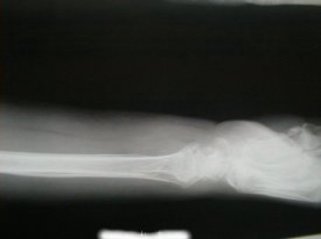

右前腕骨骨折

負傷日時 平成13年11月26日

自宅寝室からトイレに行きしなに、廊下で転倒した際に手をつき負傷

受傷時撮影1 受傷時撮影2